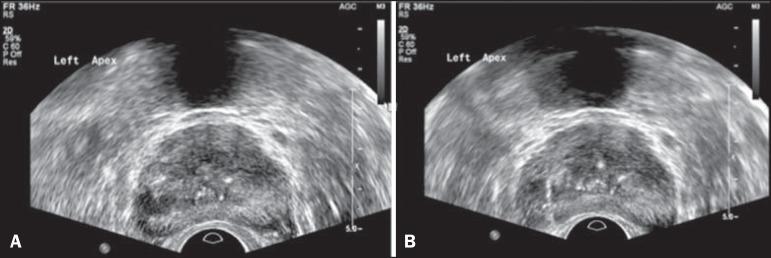

The present study was aimed at evaluating the contribution of transrectal prostate ultrasound in the screening for prostate neoplasias and in the guidance of prostate biopsies.

Prospective study developed over a one-year period. All the patients with indication for prostate biopsy were evaluated. Regardless of PSA values, the patients underwent ultrasound in order to identify suspicious nodules (confirmed by two observers). Sextant biopsy was subsequently performed. In cases of finding suspicious nodules, an additional puncture directed to such nodules was done.

In a total of 155 cases the prevalence of malignancy was of 53%. Suspicious nodules were detected in 34 patients, and 25 where malignant (positive predictive value of 74%). The specificity and sensitivity for suspicious nodules were 88% and 31% respectively. Comparatively with the randomly obtained sextant specimens, the rate of findings of neoplasia was higher in the specimens obtained with puncture directed to the nodule (p = 0.032). No statistically significant difference was observed in the Gleason score for both types of specimens (p = 0.172).

The high positive predictive value and the high rate of findings of neoplasia in specimens of suspicious nodules should be taken into consideration in the future. The authors suggest a biopsy technique similar to the one described in the present study (sextant biopsy plus puncture directed to the suspicious nodule).